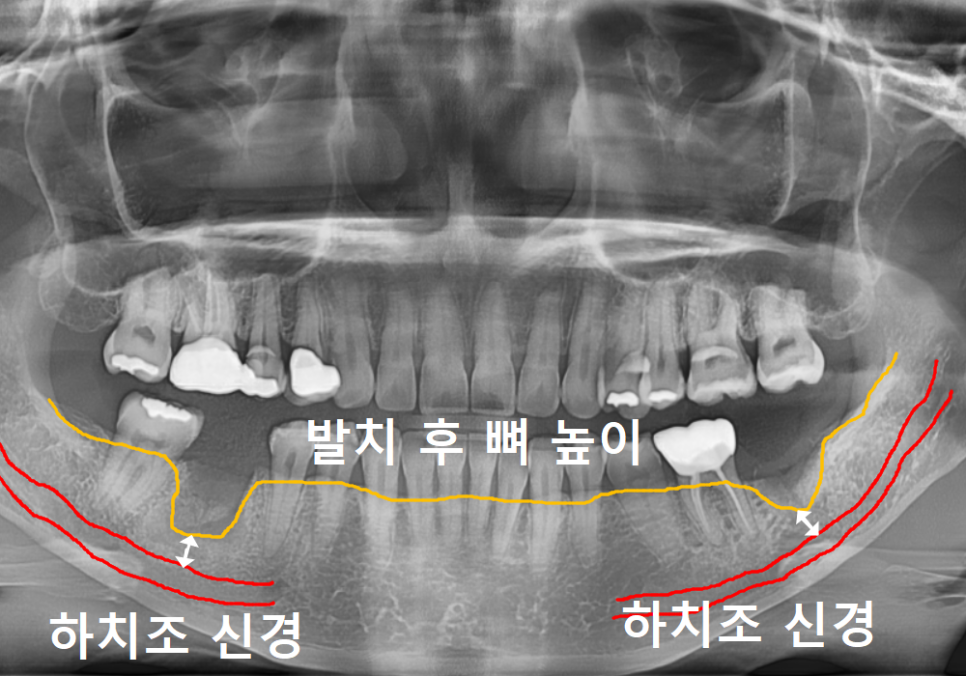

더 자세히 살펴보기 위해 CT를 확인해 보니,

뿌리 끝 염증이 까맣게 퍼져 있었는데요.

특히 치아 뿌리 바로 아래를 지나가는

'하치조 신경' 근처까지 뼈가 녹아 있었습니다.

하치조 신경은 얼굴의 감각을 담당하는

아주 중요한 통로예요.

만약 임플란트를 심다가

이 신경을 건드리면

마비나 통증이 올 수 있어

정말 조심해야 하는 구조물이죠.

250327

이 환자분처럼 신경과 가까운 곳의

뼈가 다 녹아버린 상태에서

무리하게 임플란트를 심으면 어떻게 될까요?

신경을 피하려다 보니

임플란트가 뼈에 박히지 못하고

거의 허공에 떠 있는 상태가 되어버립니다.

당연히 튼튼하게 고정될 수가 없겠죠~?